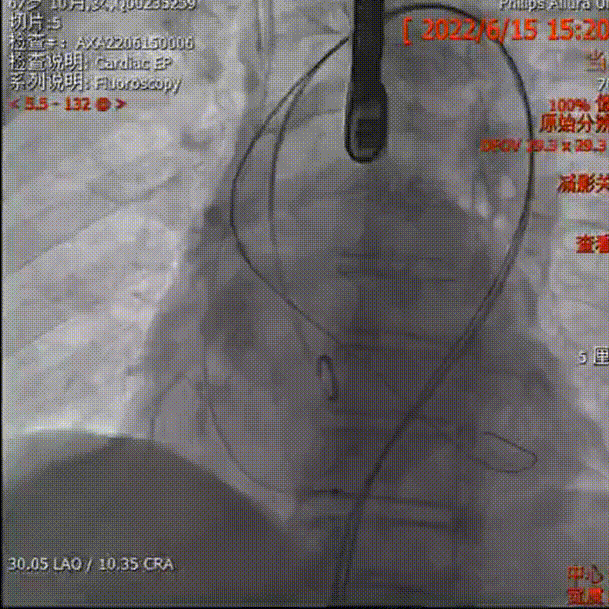

2.根据当前影像及测量数值,推荐 LAO 30° CRA 10°(右窦中心位)左右跨瓣;

主动脉根部造影

检查挂角

导丝跨瓣